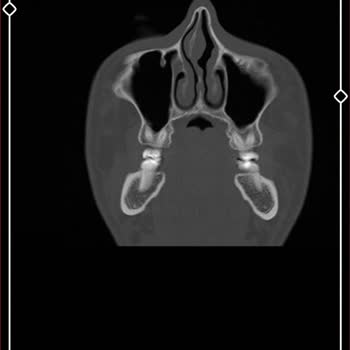

Karın ve kasık ağrısı şikayetiyle başvurduğum Kırıkkale Yaşam Hastanesi’nde, ne yazık ki beklediğim ilgiyi ve özeni göremedim. Yapılan kasık ultrasonu sonucunda, Radyoloji Uzmanı Dr. S***** S***** tarafından 'kasık fıtığı' teşhisi konuldu ve bu doğrultuda ameliyat olmam gerektiği söylendi. Rapor son...